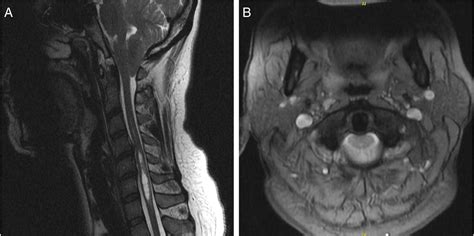

To confirm the presence of Cerebellar Tonsillar Ectopia, physicians rely heavily on high-resolution imaging. The diagnostic process is essential for differentiating between simple ectopia and other structural pathologies. The following table summarizes the primary tools used in evaluation:

Magnetic Resonance Imaging (MRI) Gold standard for visualizing the brain and spinal cord structure.

CT Scan Examines the bony anatomy of the cranium and cervical spine.

When conservative measures fail to provide relief, a procedure known as a posterior fossa decompression may be recommended. During this surgery, the surgeon removes a small piece of bone at the back of the skull (and sometimes the top of the first cervical vertebra) to create more room for the cerebellum and restore normal CSF flow. This helps alleviate the pressure and allows the brain to function without the constant constraint of the bony environment.